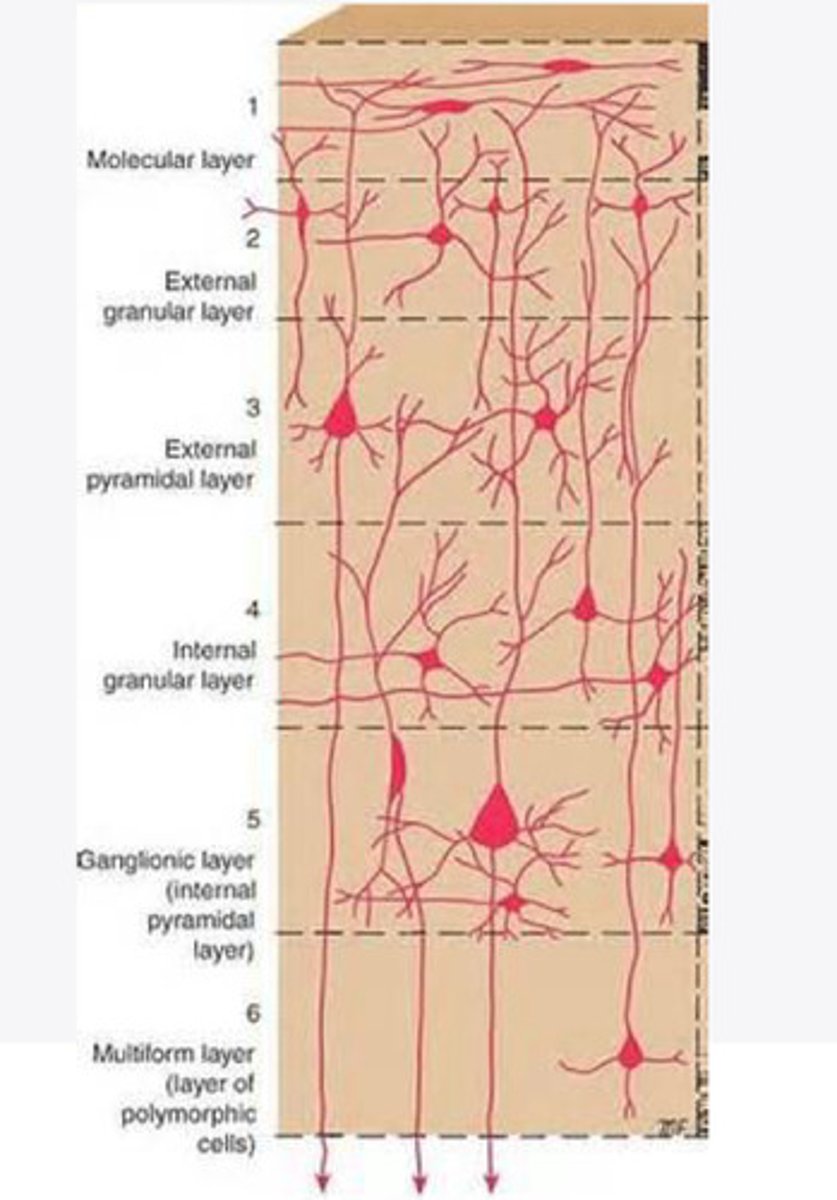

divided into 6 distinct layers, due to varying densities of cell body types within each layer

The cortex of the brain is divided into how many layers? Why is it divided into layers?

Layers of the cortex of the brain pic

2 and 4

What are the layers of the cortex that are associated with input?

3 and 5

What are the layers of the cortex that are associated with output?

molecular layer

What is the name of Layer 1 of the cortex of the brain?

very few cells

Does Layer 1 of the cortex have a lot or few cells?

receives dendrites from internal layers so it may actually function as a coordinating center where layers can communicate action

What does Layer 1 of the cortex do?

1

Every layer sends densities to Layer ____?

1

What layer serves as the "water cooler" of the brain?

external granular layer

What is the name for layer 2 of the cortex of the brain?

receives input from other cortical regions

What is the function of Layer 2 of the Cortex of the brain?

Stellate

What type of cells (stellate/pyramidal) would be most concentrated in Layer 2?

external pyramidal layer

What is the name for layer 3 of the cortex of the brain?

sends output to the other cortical layers

What is the function of Layer 3 of the cortex of the brain?

pyramidal

What type of cells (stellate/pyramidal) would be most concentrated in Layer 3 of the brain?

Layers 2 and 3

What layers are associated with association and commissural fibers?

Layer 3 - axons of cell bodies

Layer 2 - synapse into target areas in Layer 2

What part of the axons is in Layer 2/ in layer 3?

Layer 3 - external pyramidal layer

All axonal cel bodies for association and commissural fibers lie within what layer of the Cortex of the brain?

internal granular

** or called the striate cortex because it is so thick that you can see a line through this layer even in unstrained brain slides

What is the name for the 4th layer of the cortex of the brain?

receives input from the thalamus, geniculocortical layer, and other brainstem areas

What is the function for the 4th layer of the Cortex of the brain?

very thick within the vision, auditory, and somatosensory areas

Is Layer 4 thick or thin within SENSORY areas of the cortex?

Internal pyramidal

What is the name for Layer 5 of the cortex of the brain?

sends axons to the brainstem (corticobulbar) and spinal cord (corticospinal)

What is the function of Layer 5 of the cortex of the brain?

in motor areas of the cortex?

Where is layer 5 very thick in the brain?

the frontal lobe -- very motor heavy

What lobe of the brain will have a thick layer 5 of the cortex of the brain?

the multiform layer

What is the name of layer 6 of the cortex of the brain?

-sends axons back to the thalamus through corticogeniculate fibers

-modulates what information the thalamus sends to the cortex to control the strength of the signal received and modulate what you pay attention to

What is the function of layer 6 of the cortex of the brain?

no

Is layer 6 a motor layer?